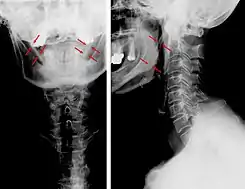

![]() Vistas lateral y anteroposterior de una radiografía cervical que muestra osificación del ligamento estilohioideo. | ||

La apófisis alargada o calcificación del ligamento estilohioideo suelen mostrarse fácilmente a través de una prueba radiográfica. De forma adicional se puede realizar un TAC para confirmar el diagnóstico y ver qué estructuras están siendo afectadas.[10]